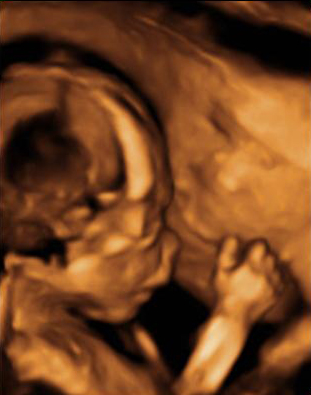

Esta imagen de una ecografía en 3D en la semana 20 de gestación al feto se le distinguen los huesos de los brazos y del cráneo, así como las fontanelas. Estas son aberturas en los huesos del cráneo que van a permitir que se superpongan cuando el bebé atraviese el canal del parto al nacer.

Si nos fijamos se nota la fontanela y los huesos craneales. También se ven de forma nítida los huesos del brazo: húmero, cúbito y radio.